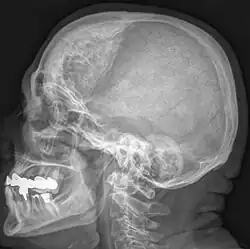

Hyperostosis frontalis interna

| Hyperostosis frontalis interna in a 74-year-old woman | |

Hyperostosis frontalis interna is a common, benign thickening of the inner side of the frontal bone of the skull. It is found predominantly in women after menopause and is usually asymptomatic. Mostly frequently it is found as an incidental finding discovered during an X-ray or CT scan of the skull.